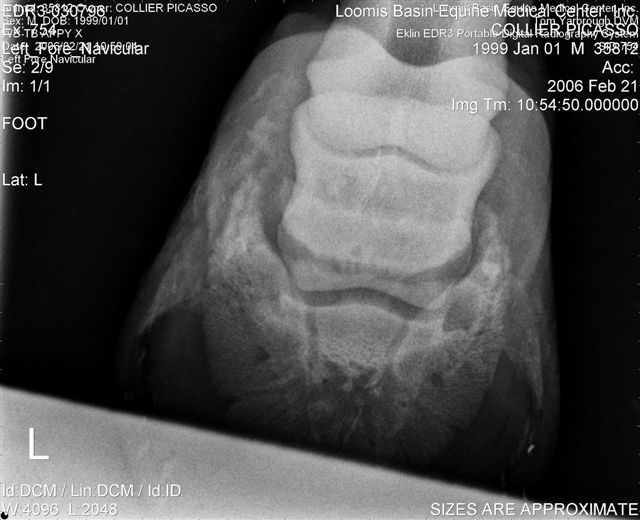

Let's label the radiographs from left to right with numbers. The abnormalities I see on the L using the photo's number as reference:

1) Odd lucency (darker) at the top/lateral margin of the coffin bone (seen in many images). It would interesting if this is also the site of the odd bruising.

2) Decrease lucency (darker) in the body of the navicular bone.

2) Remarkable cone shape areas of decrease lucency (darker) along the distal margin of the navicular bone.

3) Assymetrical flexor surface of the navicular bone.

4) There is the appearance of poor ap balance of the foot with the heels being low

4) Soles appear thin

4) Small osteophyte (bone spur) on the front margin of the pastern joint.

On the right the main problem is the appearance of the n. bone in the first image. It appears to have large irregular areas of increased lucency surrounding areas of decreased lucency. The darker areas (decreased lucency) may be artifacts or represent thinning of cortical bone.

Unless there is something I am missing in the images the extensor process appears to have healed well on the L. The significance of each of these lesions will depend on clinical findings Ann and confirmation that these are actual lesions and not artifacts created by positioning or the foot preparation for radiography. You should note I am not a radiologist and that viewing images in this manner is not as revealing as viewing the radiographs first hand.